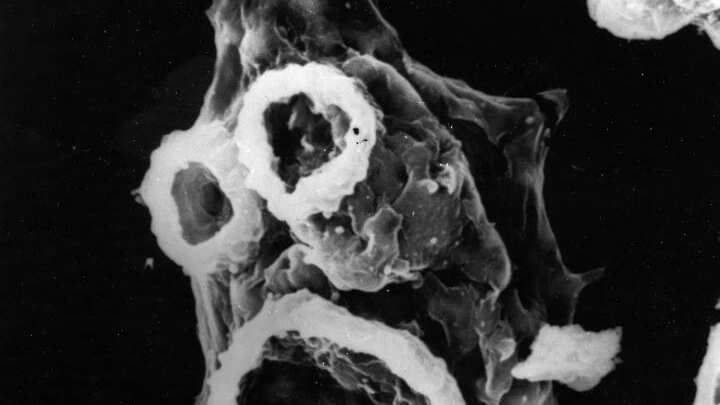

La Naegleria se encuentra en cuerpos de agua cálidos, como lagos, ríos y hasta aguas termales. También puede encontrarse en el suelo. Sin embargo, solo un tipo de esta bacteria afecta a los humanos: la Naegleria fowleri.

“Los síntomas iniciales comienzan aproximadamente 5 días (aunque el rango puede ser de 1 a 9 días) después de la infección. Estos pueden incluir dolor de cabeza, fiebre, náuseas o vómitos. Los síntomas posteriores pueden incluir rigidez en el cuello, confusión, falta de atención a las personas y los alrededores, pérdida del equilibrio, convulsiones y alucinaciones. Después del inicio de los síntomas, la enfermedad progresa rápidamente y generalmente causa la muerte en aproximadamente 5 días (rango de 1 a 12 días)”, agregan los especialistas.